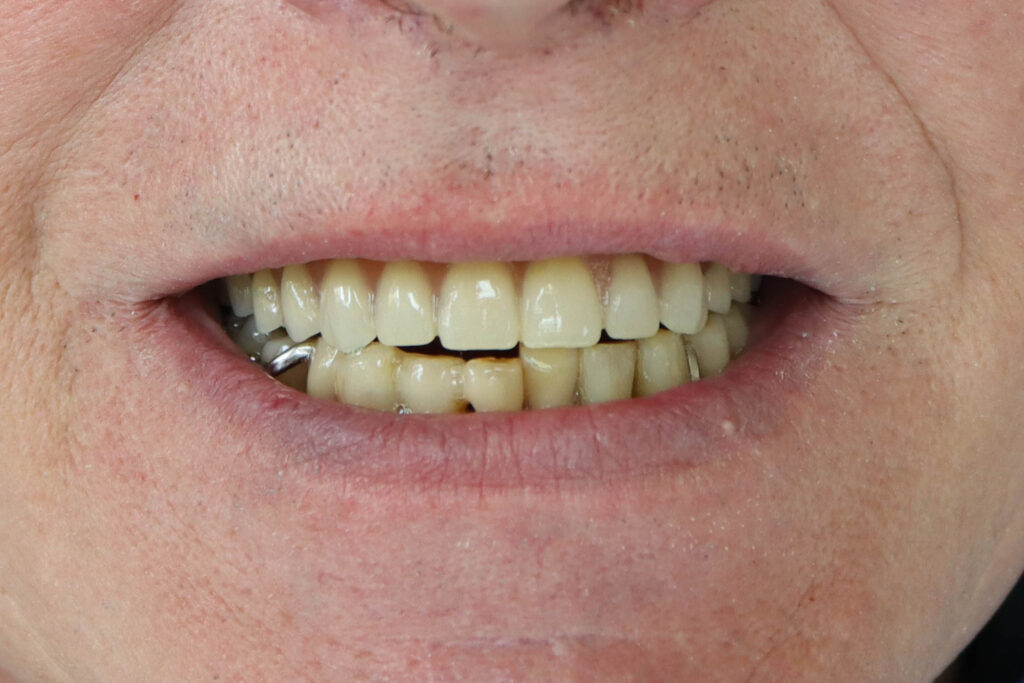

Результат

результат имплантации

работы врача